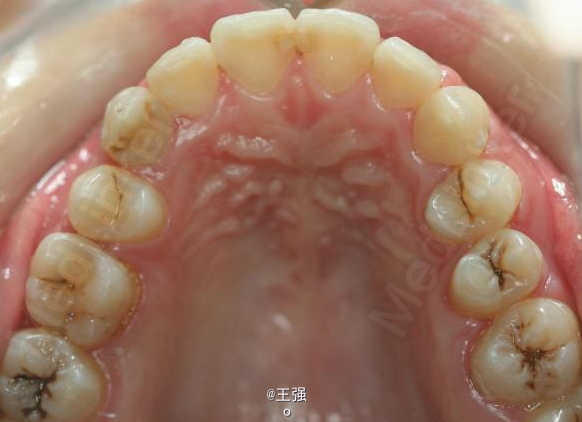

又一例不对称拔牙

牙弓狭窄,牙列拥挤

不对称拔牙